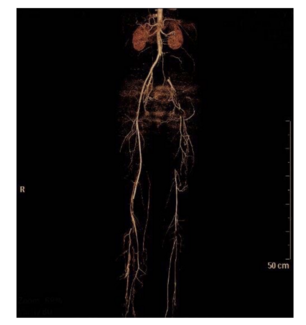

The authors present the case of a patient with neurological deficits in the setting of TAAD with compromise of the common carotid arteries.